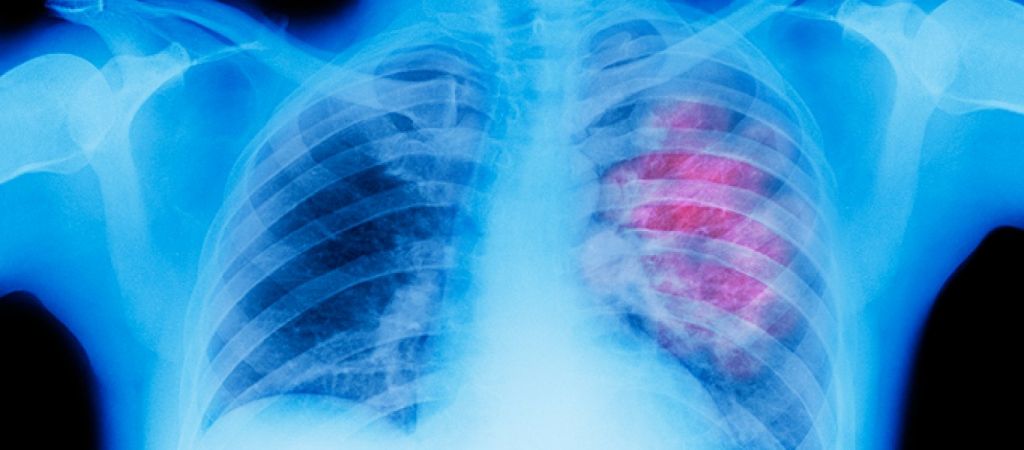

Οπως αποκαλύπτει η εφημερίδα της Μαγνησίας Ταχυδρόμος,  είναι σε εξέλιξη ερευνητικό πρόγραμμα στην κατεύθυνση της πρώιμης και έγκαιρης διάγνωσης του καρκίνου του πνεύμονα. Το συγκεκριμένο ερευνητικό πρόγραμμα υλοποιείται στην Ιατρική Σχολή του Πανεπιστημίου Θεσσαλίας με τη συνεργασία του Εργαστηρίου Επιδημιολογίας και της Πνευμονολογικής Κλινικής του Πανεπιστημιακού Γενικού Νοσοκομείου Λάρισας.

Η ανάλυση του εκπνεόμενου αέρα του κάθε ατόμου που εξετάζεται, αναδύεται ως μια πολύ υποσχόμενη, μη επεμβατική, λιγότερο απαιτητική και σημαντικά φθηνότερη μέθοδος για την πρόωρη διάγνωση του καρκίνου του πνεύμονα και ακόμα για τον προληπτικό έλεγχο του πληθυσμού. Βασίζεται στην ανίχνευση και τον ποσοτικό προσδιορισμό στην εκπνοή των χαρακτηριστικών πτητικών οργανικών ενώσεων (Volatile Organic Compounds-VOCs) που υποδεικνύουν την παρουσία της νόσου.

Το συγκεκριμένο πρόγραμμα βρίσκεται σε ερευνητική φάση, όπως αναφέρει στον ΤΑΧΥΔΡΟΜΟ ο καθηγητής Κωνσταντίνος Γουργουλιάνης, διευθυντής της Πνευμονολογικής Κλινικής, ο οποίος υπογράμμισε ότι είναι πάρα πολύ σημαντικό, διότι γίνεται πολύς λόγος για το «πώς μπορεί να διαγνώσει κανείς έγκαιρα τον καρκίνο του πνεύμονα και να παρακολουθήσει τη νόσο χωρίς επεμβατικές τεχνικές, από τον αέρα που εκπνέει κάποιος».